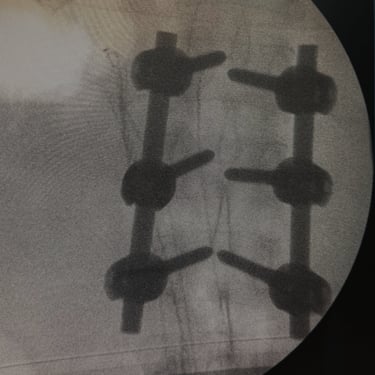

Fractura Vertebral Lumbar: Estabilización Segura con Fijación Transpedicular (FTP)

La fractura vertebral lumbar es una lesión que puede comprometer la estabilidad de la columna y las estructuras neurológicas. En casos seleccionados, el tratamiento quirúrgico mediante artrodesis con fijación transpedicular (FTP) ofrece una estabilización sólida de los segmentos afectados, restaurando la alineación vertebral y permitiendo una movilización temprana. Esta técnica reduce el dolor, previene deformidades progresivas y protege las raíces nerviosas. La intervención oportuna, acompañada de una adecuada rehabilitación, contribuye a una recuperación funcional segura y a una mejora significativa en la calidad de vida del paciente.